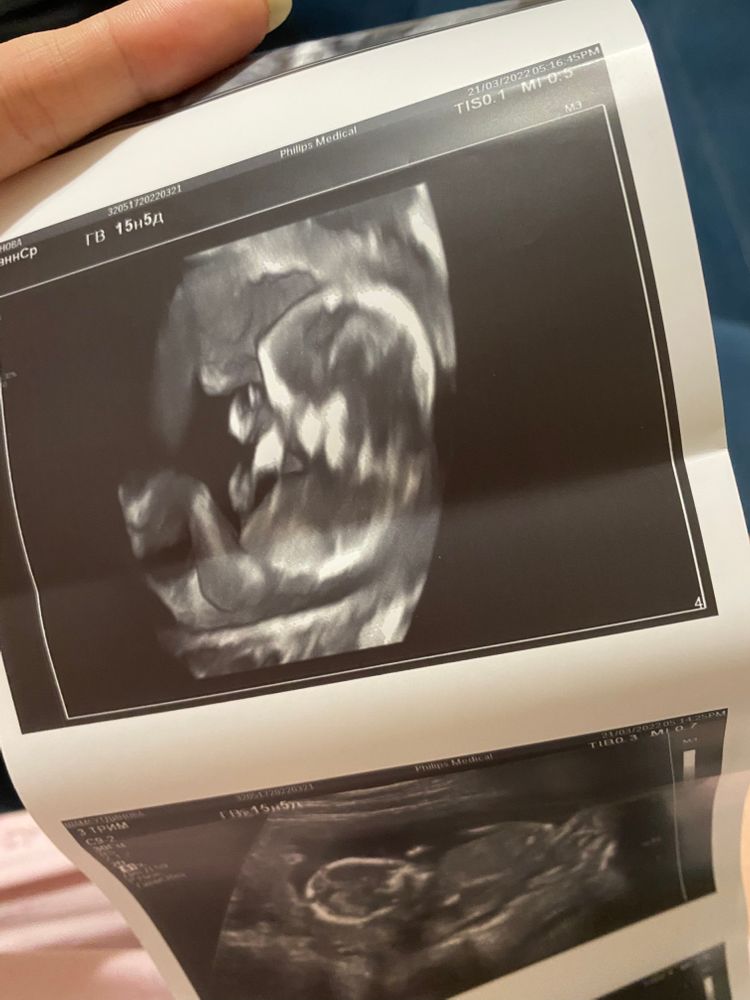

Привет!)Девочки кто как думает, кто в животике: мальчик или девочка?🥰 так интересно , хотя без разни

Пол малыша

Девочка)бугорочек лежит 🌺

А мне почему-то кажется что мальчик, у нас в 12 неделек похожий бугорок был, думали тоже девчушка, А оказался мальчишка ☺